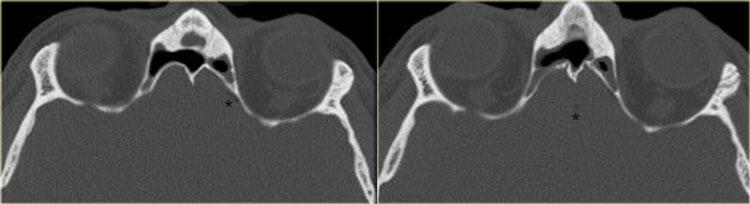

Bên trái là hình ảnh CT của một bệnh nhân sau ghép phổi có sốt và liệt nhiều dây thần kinh sọ tiến triển nhanh.

Chúng tôi sẽ trình bày hình ảnh CT và MRI của bệnh nhân này. Chẩn đoán u lympho được xác định qua sinh thiết.

Trên hình ảnh CT, các phát hiện bao gồm:

- Khối mô mềm trong xoang hàm (mũi tên đỏ).

- Phá hủy thành xoang (mũi tên vàng).

- Tái cấu trúc và phá hủy xương chân bướm (mũi tên xanh dương).

- Khối mô mềm lớn trong khoang cơ nhai (dấu hoa thị).

Hình ảnh bên phải ở mức cao hơn.

Có hình ảnh mờ đục xoang bướm kèm phá hủy và loãng xương bướm.

CT thể hiện rõ sự phá hủy xương và một phần xâm lấn mô mềm.